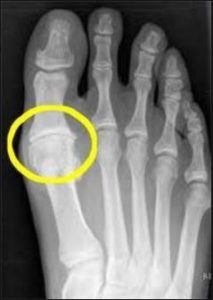

Große Zehe Arthritis

Schwellung, Ballenzehen und Knochensporne in der großen Zehe können eine Nervenkompression und Taubheit verursachen (1).

Arthritis in der großen Zehe verursacht eher Steifheit oder Schmerzen als Taubheit. Ballenzehen, die oft durch ein Problem im unteren Rücken verursacht werden, können Druck auf umliegende Strukturen ausüben und dabei Taubheit in der großen Zehe erzeugen. Sehnenverletzungen sollten ebenfalls in Betracht gezogen werden, wenn die Ursache der Taubheit ermittelt wird, insbesondere wenn weitere Symptome wie abwechselnde Schmerzen und Taubheit vorhanden sind.

Bei Arthritis der großen Zehe ist eine Großzehenfusion, bei der zwei oder mehr Zehenknochen miteinander verschmolzen werden, um sie unbeweglich zu machen, oder das Entfernen und Ersetzen des Großzehengelenks, oft die chirurgische Lösung. Diese invasiven größeren Operationen führen zu langen Erholungszeiten und können mehr Probleme verursachen, als sie lösen.